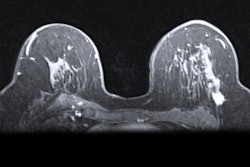

Dr. Hannah Chung."The reason that there's so much interest in breast MRI is that it's the most sensitive imaging modality we have," Gilbert said. "It's the best technique for picking up breast cancer."

MRI's unparalleled sensitivity could be why the modality is still a "hugely popular" topic at this year's conference, according to Gilbert. She highlighted a number of applications drawing interest among the research community, including abbreviated protocols to shorten scan time and the use of MR for dense breasts.

However, MRI has its own drawbacks. Chung noted that breast MRI has a long scan time, and some patients may have issues with the closed physical space of the magnet bore. In addition, the long-term effect of repeated gadolinium contrast is unknown, a problem that could be compounded with the use of MRI for screening.